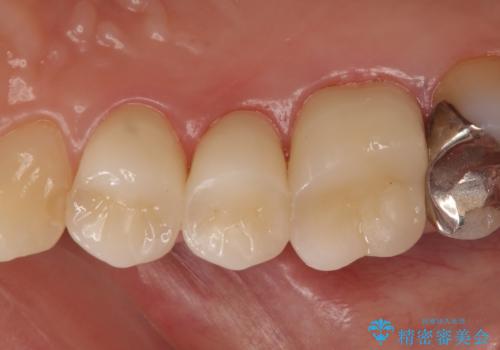

検査の結果右上5の歯の神経が死んでいたため、根管治療を行った後に、オールセラミッククラウンによる補綴を行いました。

また右上6に関しては再根管治療を行い、右上4に関しては虫歯治療を行った後に、オールセラミッククラウンによる補綴を行いました。

今回用いたオールセラミッククラウンはジルコニアフレームという白い素材の上にセラミックを盛っているため、審美性が非常に高いのが特徴です。

また、ジルコニアは人工ダイヤモンドの材料にも使われているほど高い強度を持っており、そのためオールセラミッククラウンは審美性だけでなく、奥歯やブリッジの補綴も可能とするクラウンです。